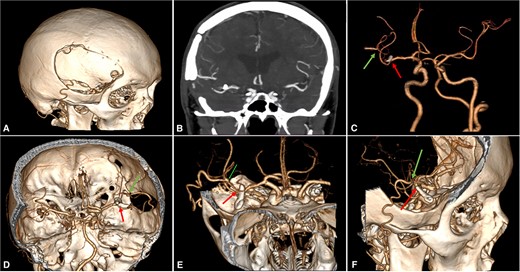

A 46-year-old male with a past medical history of arterial hypertension presented with a 4-month history of recurrent and sporadic headaches, transient ischemic stroke, and a recent 3-day course of left hemiparesis. Neurological examination showed mild 4/5 left-sided hemiparesis and a Glasgow coma scale (GCS) score of 15. A subsequent cerebral angiotomography revealed an unruptured 25 × 10 mm fusiform aneurysm in the superior M2 segment of the MCA (Fig. 1). After discussing potential risks, benefits, and natural history with the patient, we decided to perform a superficial temporal artery (STA) to M3 bypass with proximal occlusion of the giant fusiform aneurysm.

Cerebral Angiotomography. (A) Posterior view depicts an unruptured giant fusiform aneurysm in the M2 segment of the right MCA; (B) Anterior view reveals a close aneurysm proximity to the M1 segment of 3 mm; (C) Complex architecture of the giant fusiform aneurysm is shown with adjacent M2 and M3 branches. MCA: middle cerebral artery